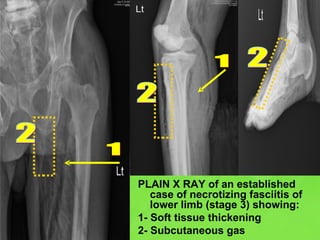

PLAIN X RAY of an established case of necrotizing fasciitis of lower limb (stage 3) showing: 1- Soft tissue thickening 2- Subcutaneous gas 1 1 2 2 2

PLAIN X RAYof an established case of necrotizing fasciitis of lower limb (stage 3) showing: 1- Soft tissue thickening 2- Subcutaneous gas 1 1 2 2 2